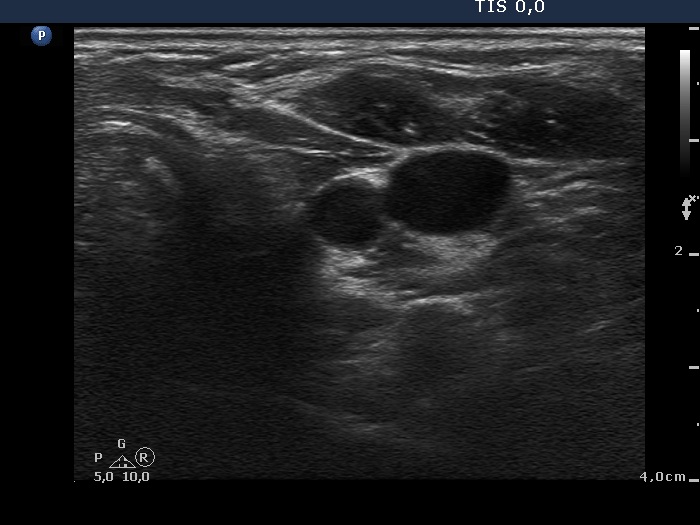

Ultrasonography. The right thyroid was moderately hypoechogenic without any circumscribed lesions. The left thyroid was removed. There were several enlarged lymph nodes in the right submandibular area. The largest one presented two discrete, more hypoechogenic intranodal lesions and a regular hilum.

Comment. This is an unusual case, the nodes (particularly those presented in the video) seem to be benign, reactive-type ones.